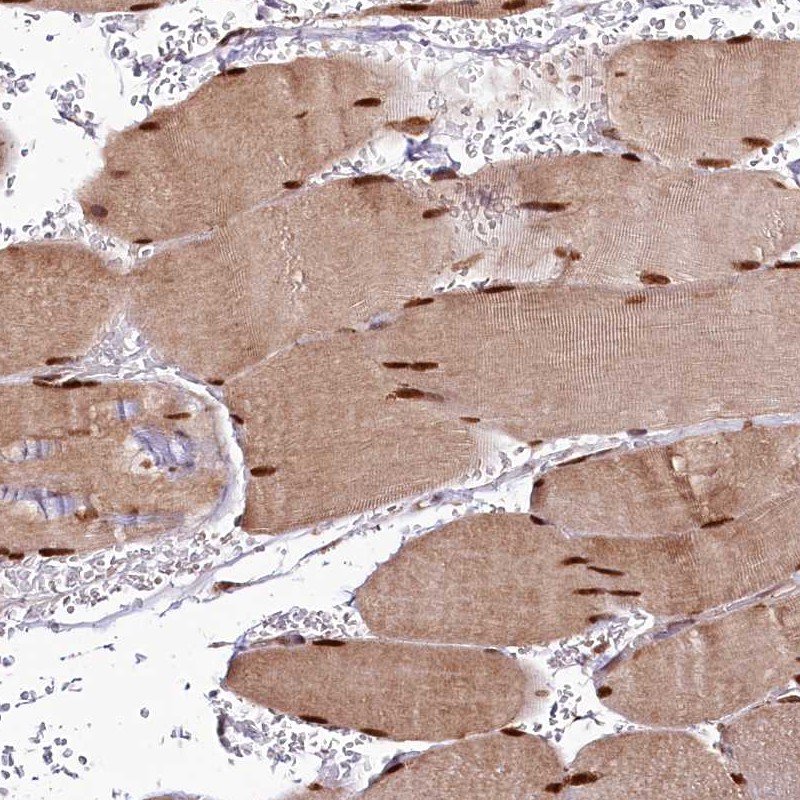

Immunohistochemical staining of human skeletal muscle shows strong nuclear staining and slightly weaker cytoplasmic positivity in myocytes.